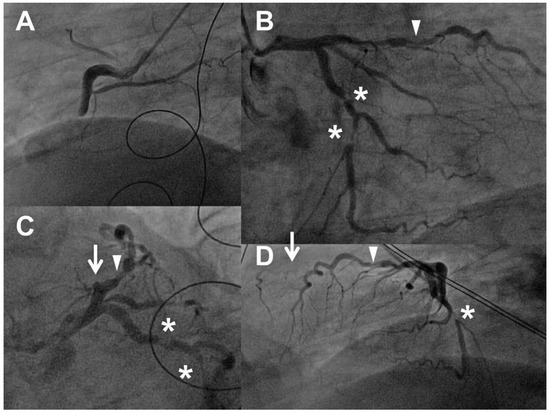

Angiography revealed an acute occlusion of the mid RCA (Figure 4 panel A). In addition, there was chronic occlusion of the mid left anterior descending artery (LAD; Figure 4 panels B and D, arrows) just distal to the ostium of a large diagonal branch, which was also significantly stenotic (Figure 4 panels B and C, triangle). Furthermore, the left circumflex artery had two significant stenoses (Figure 4 panels B–D, asterisks).

Figure 4. Angiogram before percutaneous coronary intervention. Panel A, left anterior oblique (LAO) 60°: acute occlusion of the mid-right coronary artery (RCA). Panel B, right anterior oblique (RAO) 30%, caudal 20%: left circumflex artery (LCX) with two significant stenoses (asterisks), first diagonal branch with significant lesions (triangle), the left anterior descending artery (LAD) in its typical course is not visible as it is occluded. Panel C, LAO 40%, caudal 30% (“spider view”): chronic occlusion of the mid LAD (triangle), significant stenosis of the first diagonal branch (triangle), two severe stenoses of the LCX (asterisks). Panel D, LAO 90%: the typical clinical course of the LAD is not visible (arrow), i.e. the vessel is occluded, severe LCX stenosis (asterisk).